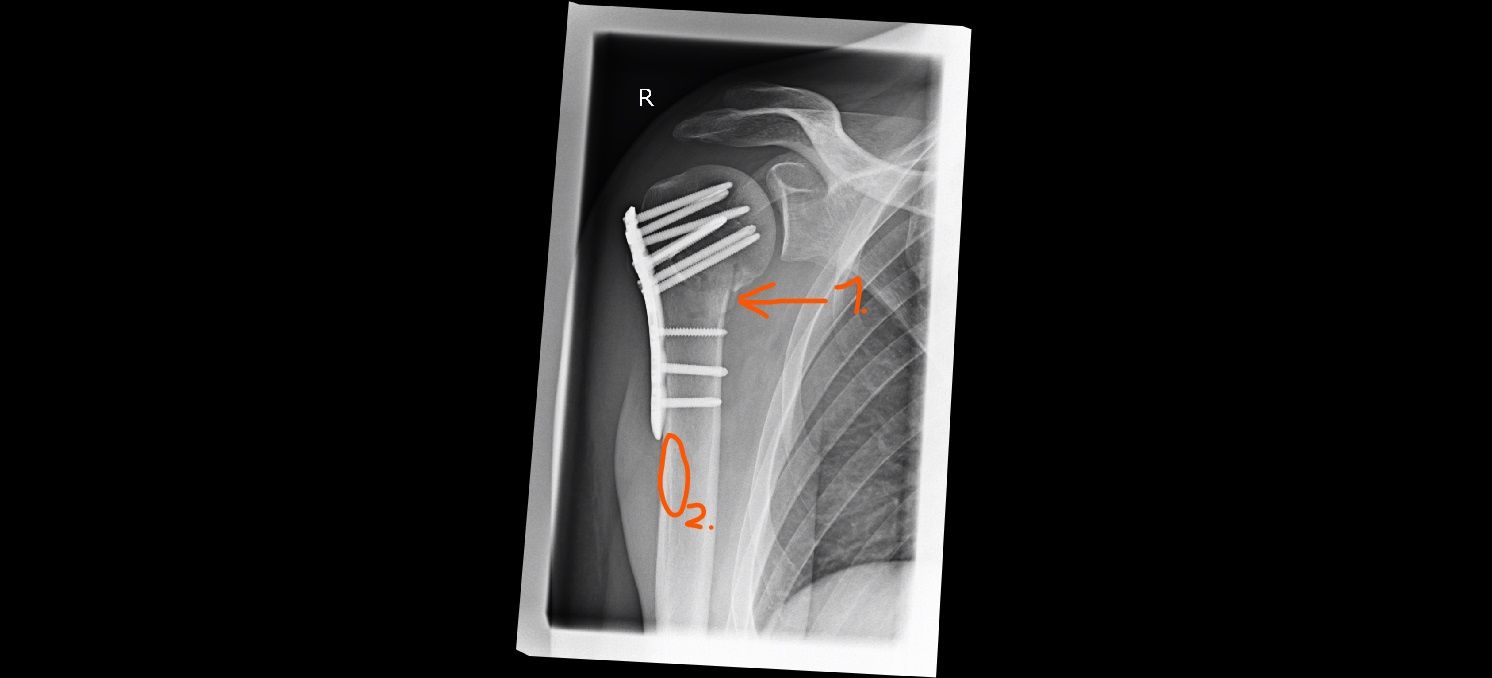

Hmmm... Finde den Unterschied...

Auf der ersten Aufnahme (Seite 3) stand bei 1. etwas vom Knochen ab, was bei der neuen Aufnahme jetzt wieder am Knochen dran ist. Bei 2. war auf dem ersten Bild ein dunkler Streifen zu sehen, der bei der neuen Aufnahme nicht mehr zu sehen ist. Allerdings ist das ganze schwer zu vergleichen, auf der älteren Aufnahme sieht man die Stabilisierungsplatte etwas schräg seitlich, auf der zweiten Aufnahme genau von der Seite.

Hier nochmal zum Vergleich die alte Aufnahme:

Anhang anzeigen 952916